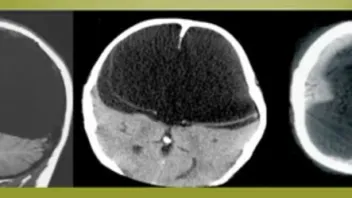

Aber mal im Ernst - selbst wenn Dein Gehirn so aussehen würde, wie eines dieser drei hier, gäbe es noch keinen Grund zur Beunruhigung:

Die schwarzen Flächen bei diesen Röntgenaufnahmen bedeuten nämlich - an dieser Stelle gibt´s kein Gehirn. Da ist nix, tote Hose, das Gehirnareal rechts ist dabei sogar fast leer. Aber die Besitzer dieser Gehirne leben, haben eine Familie, einen normalen Job und sprechen teilweise mehrere Sprachen.